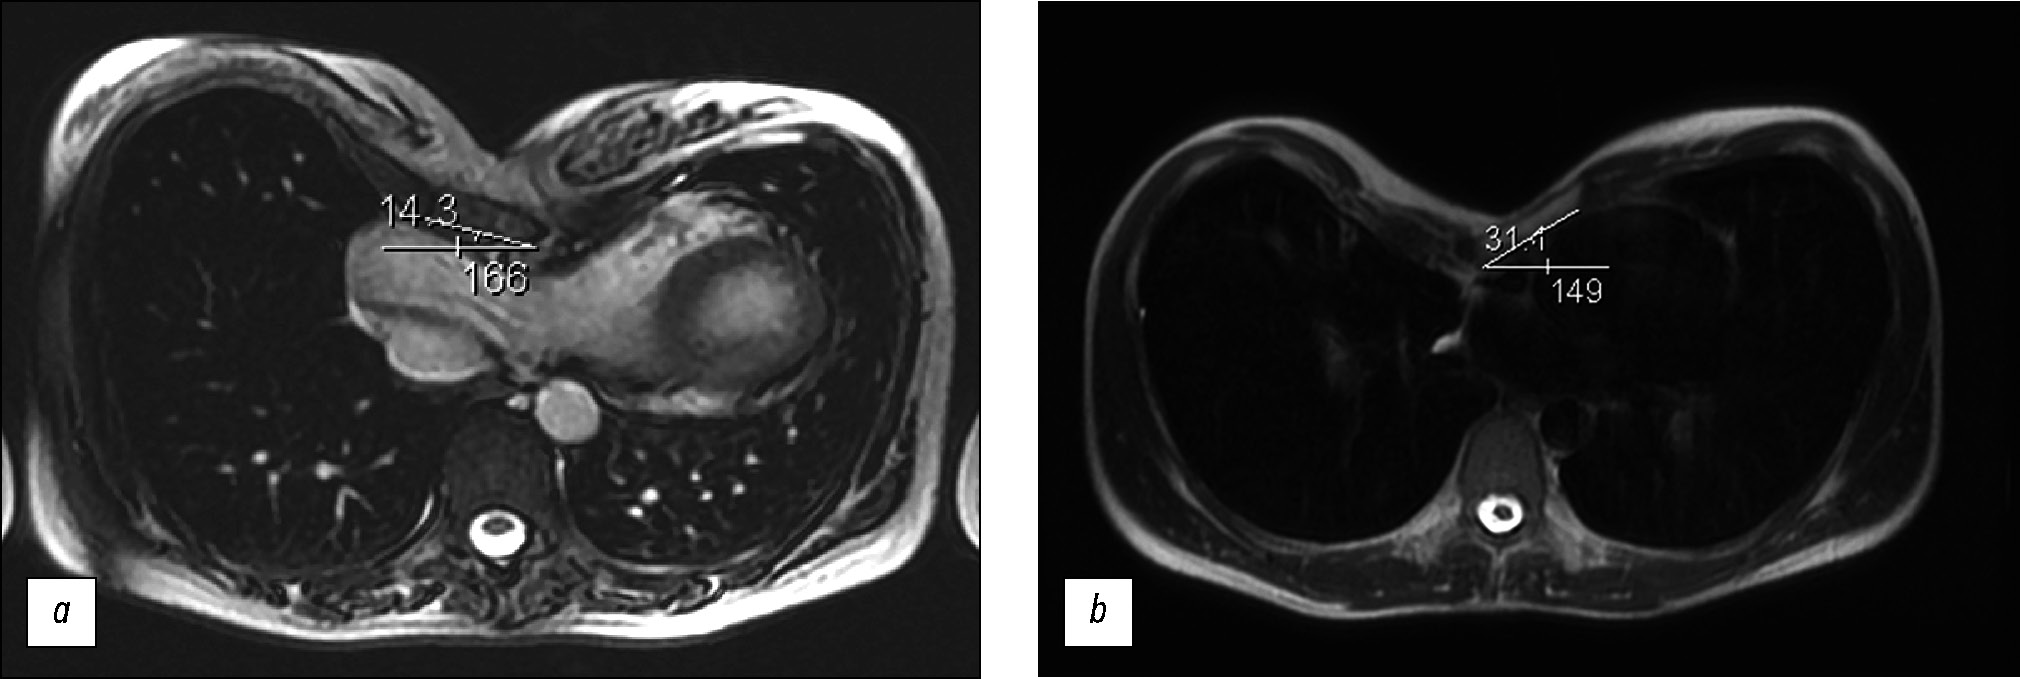

Patients were divided into three subgroups based on the Haller index (Fig. 1, Table 1). Mild PE patients did not require further surgery. The surgery was performed for patients with moderate to severe chest wall deformities.

Fig. 1. Chest magnetic resonance imaging at the level of maximum deformity; (a) the Haller index of 3.1; (b) the Haller index of 3.3; (c) the Haller index of 5.2.